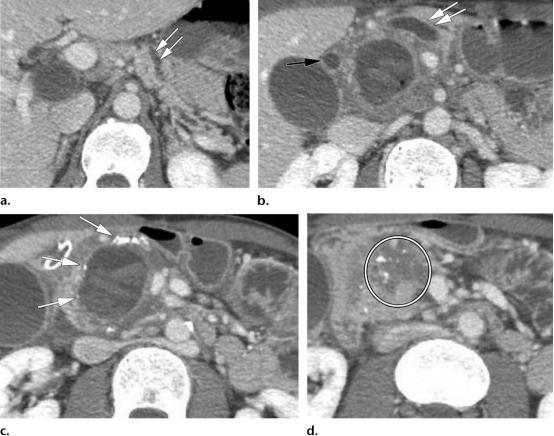

49岁女性,胰腺头部的肿块形成型慢性胰腺炎。

(a图)轴位CT示扩张的主胰管(白色五角形),胰腺实质完整保存,未见明确萎缩。胰管与胰腺实质的比值小于0.5,胰腺实质内可见散在钙化灶(白色短箭头);

(b图)冠状位CT图示,胰头区肿块样病变(白色圆圈),胰管突然变窄,并穿透于实质内(黄色长箭头)。

56岁男性,胰头区的胰腺导管腺癌(PDAC)。

(a图)轴位CT图示肠系膜上静脉(白色短箭头)与肠系膜上动脉(黑色长箭头)大小相仿,伴血管周围的软组织密度包裹(白色长箭头)。肠系膜上静脉的轮廓异常。

(b图)轴位CT图示,胰头区局灶浸润性低密度肿物,侵及胃十二指肠动脉(白色长箭头)。

(c图)轴位CT图示远端胰管的管径正常,胰腺实质也保存完好(白色短箭头),关注观察扩张的胆总管远端(白色*),未见胰腺实质背景的钙化。

43岁男性,肿块形成型慢性胰腺炎,伴假性囊肿。

(a图,b图)轴位CT示主胰管弥漫增粗(两个平行排列的白色双箭头)以及扩张的胆总管(黑色长箭头),这也称为*管双**征。胰腺实质保存完好,胰管与胰腺实质的比值小于0.5。

(c图)轴位CT图示胰头区散在钙化灶(白色长箭头),在胰头区域可见囊性病变,伴血性内容物,符合假性囊肿表现。

(d图)轴位CT图示胰头区肿块样增大(白色圆圈)